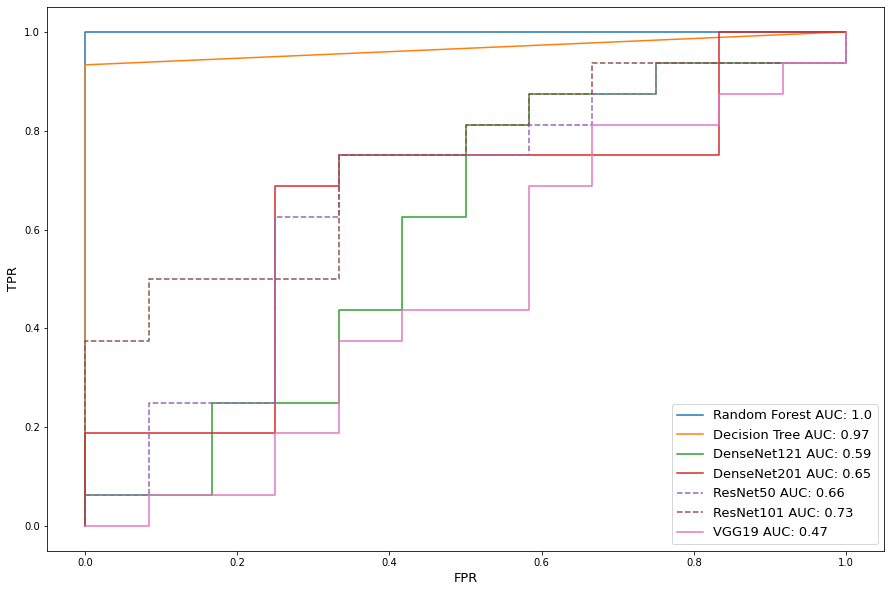

The eight models are trained without data preprocessing on all tampered images, and a subset of untampered images to balance data quantity for classes. Table 2 shows train and test performance metrics for the classifiers. The SVM, Random forest and Decision tree perform much better then deep learning models. Insufficient data severely hindered deep learning models’ accuracy due to overfiting issue. Figure 2 shows the receiver operator characteristic (ROC) curves, where TPR and FPR represent true positive rate and false positive rate respectively. The ROC curve is created by plotting the TPR against the FPR at various threshold settings, which is a commonly used plot to qualify the diagnostic ability of a classifier. The area under the curve (AUC) summarizes the quality of classification and is used as another measure of accuracy, where an AUC of 0.5 indicates a random classifier with no predictive credibility. The results show ResNet101 is able to reach 80% TPR with the hindrance of a 50% FPR rate and would be considered poor (El Khouli et al., (2009)). FPR addresses classification accuracy of tampered scans and is required to be minimized as much as possible in order to avoid life threatening misclassification. Given low quantity and high dimensional data, the bootstrap aggregation and random feature selection allow the random forest to produce a high performance. However with limited test sample presence, further testing is required to determine true accuracy levels with features at scale.

Table 4 shows the classification performance for the augmented data. We see the addition of data allows near perfect score improvement for the deep learning models. However, the increase in sample size decreased overall conventional machine learning algorithm accuracy due to a higher possibility for false predictions. This phenomenon is also reflected in Figure 6 as deep learning reached AUC scores nearing 1.0, while the Decision Tree AUC score dropped 0.05 from Figure 5.